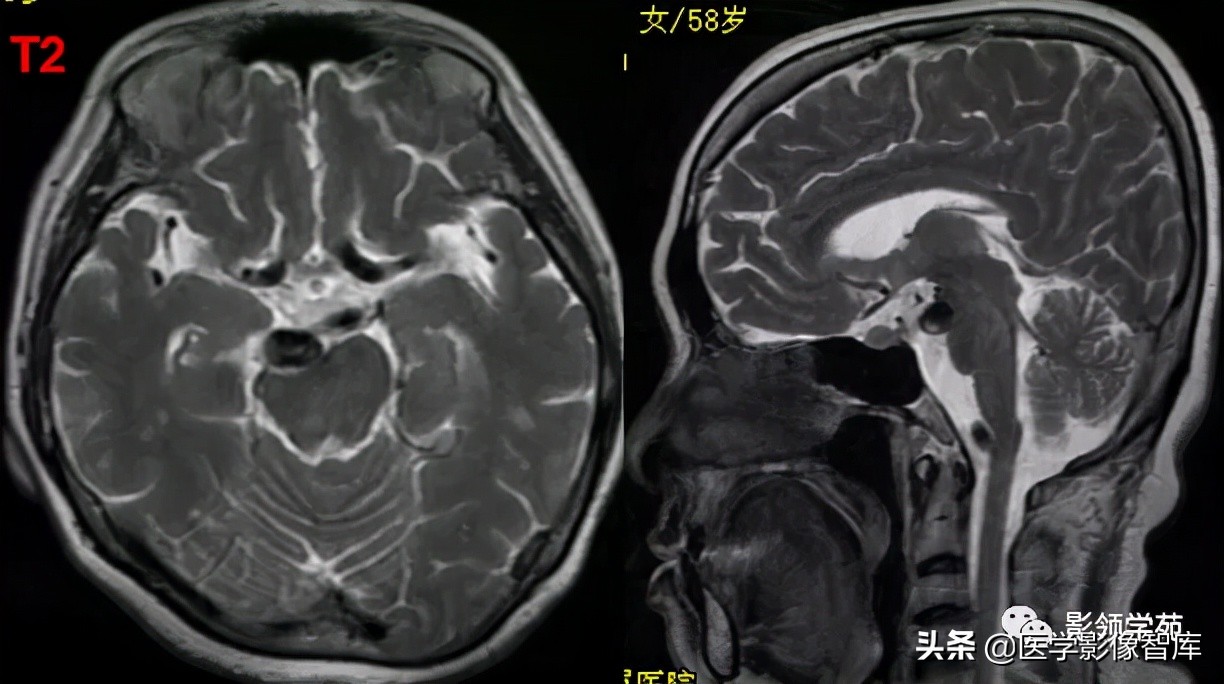

女 58岁,头晕、呕吐,桥脑右前方见一类圆形

高低混合(有血栓)T1及T2信号影,边界清楚、锐利。

明显不均匀强化(瘤内有血栓)。与基底动脉分界不清

头颅CTA:基底动脉起始部血管局部瘤样突起(宽基底),无占位效应。

女 72岁,发现糖尿病3年余

鞍上区见一团块状稍高密度影,边界尚清,密度均匀。

鞍上右上方见一类椭圆形流空影。

病灶明显强化(瘤内血栓未强化),边界清楚,与右侧颈内动脉海绵段分界不清。垂体大小、形态未见异常。